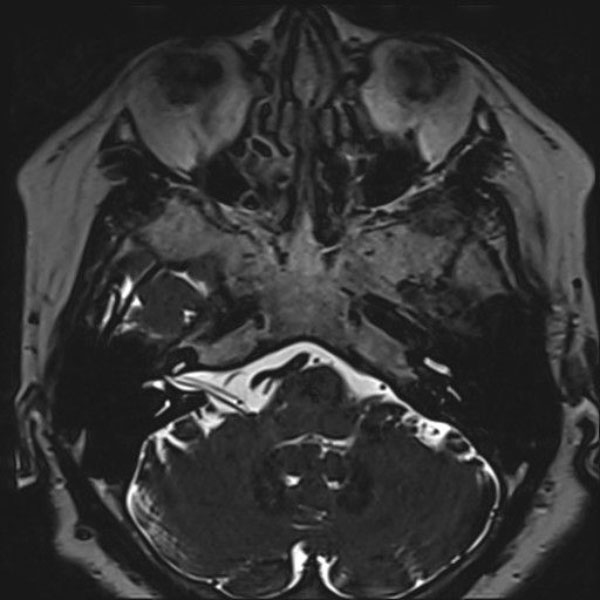

手術前

(MR1)